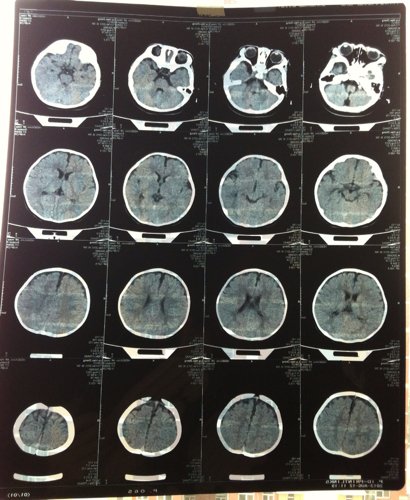

婴儿脑积水 孩子六个多月了,有一天头往一边摇和蹭脖子一样,眼睛有点向上翻,能用声音打断,去医院做

了动态脑电图和CT,脑电图没异常,CT显示:双侧额部颅板下可见窄条形水样密度,与脑组织分界清晰,脑实质内未见异常密度,脑沟、裂、池无增宽,脑室系统无扩张,中线结构居中。诊断意见:考虑轻度外部性脑积水。医生开了:小儿盐酸赖氨酸颗粒。   由于早产35+6出生三天 CT显示低密度影,医生说能吸收就没治疗。请问这病严重吗,需要住院治疗吗,从一侧摇头可能会变成癫痫吗,,他睡觉时拇指有点往里扣,抓东西、玩手时都能伸开,有的时候他还会攥着小拳头发出狠声,还有六个月20斤不会站在大人腿上跳,其他该会的会了,这都正常吗?

你好,这只是轻度的脑发育欠佳而不是脑积水,在治疗上可以使用营养脑细胞的药物来促进其恢复,修复其脑细胞,比如:脑水解蛋白,神经节苷酯,神经生长因子等等均是疗效比较好的药物,还可以同时用小儿高压氧来治疗。治疗主要抓早期,也就是脑神经发育最快的时段,在这个时段给予用最好的方法和最好的药物。避免和减轻脑瘫症...状的发生。大部分孩子可以在1岁以内好转如果超过1岁以上效果就差了。